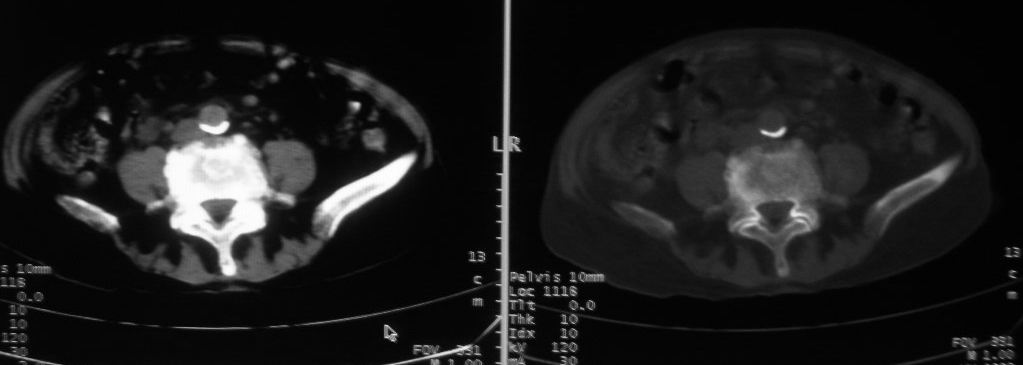

以下是引用zjzjr在2008-10-3 12:59:00的发言:[br]前列腺癌伴左髂骨\\腰椎转移可能性大.

以下是引用卜一在2008-10-3 13:40:00的发言:[br]前列腺癌!左髂骨\\腰椎转移?建议行全身骨扫描!

以下是引用深泽交通医院在2008-10-3 15:33:00的发言:[br]前列腺实性增大伴分叶状,与包膜间隙境界不清;椎体松质区间结节样密度影,考虑:前列腺癌,并椎体成骨性转移